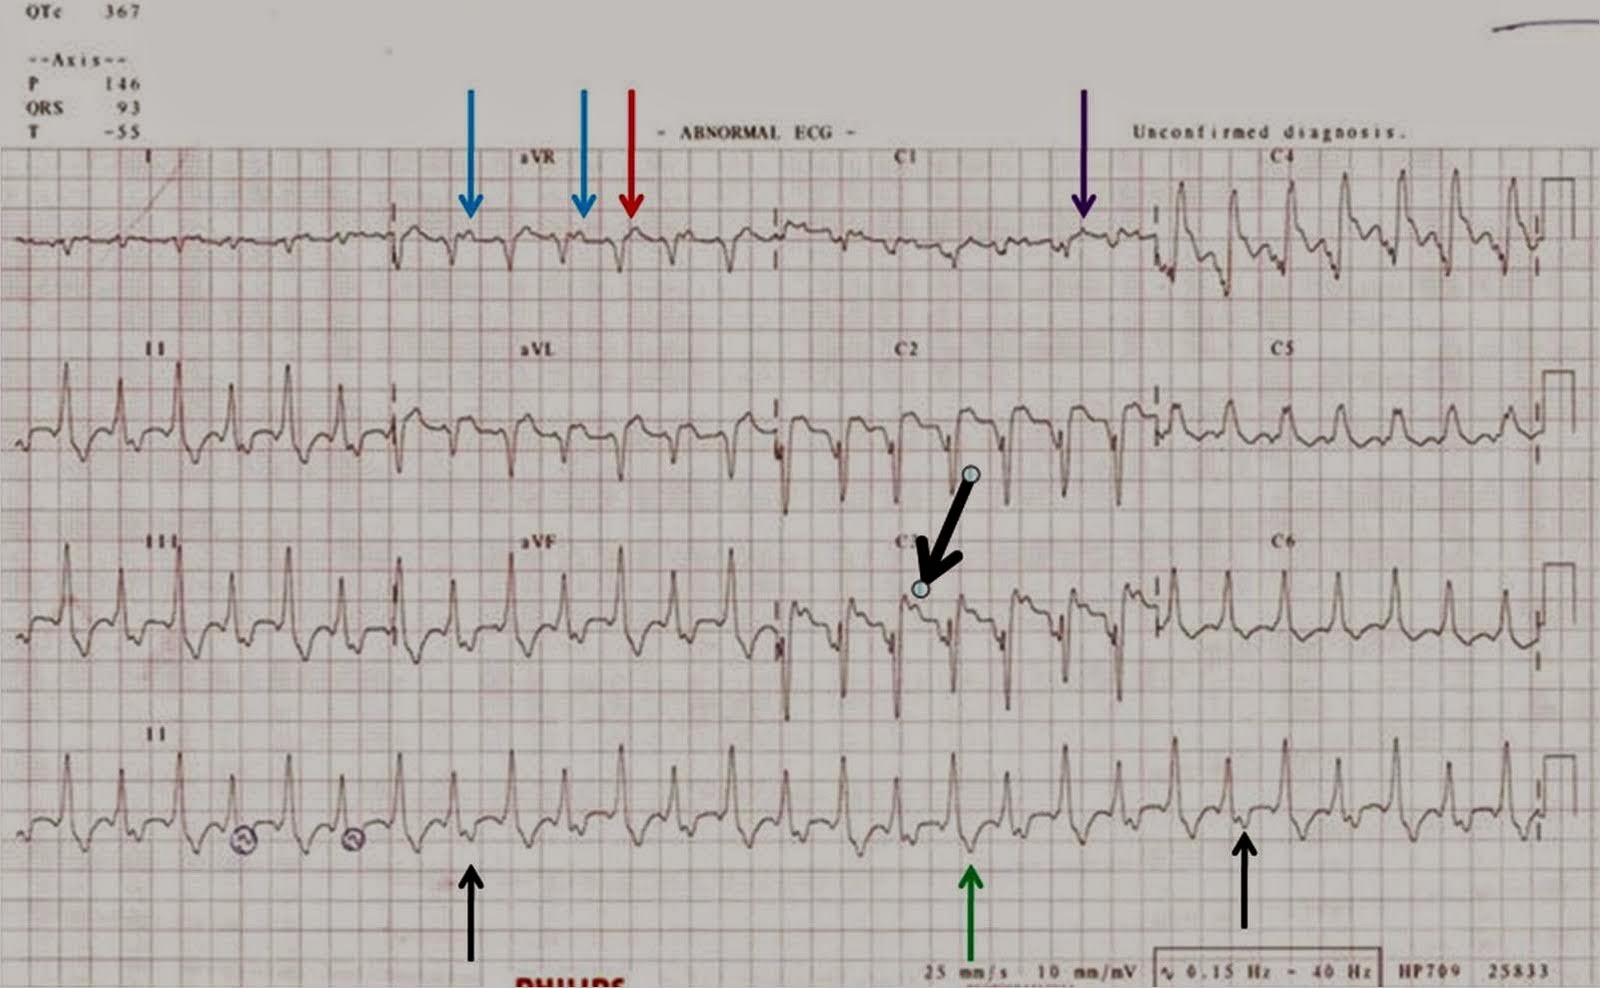

A man with chest pain and a broad QRS complex tachycardia The BMJ Sharp Chest Pain Ventricular Tachycardia Electrical signals in the heart’s. chest pain, dificulty breathing and a rapid pulse are urgent symptoms of a potentially fatal ventricular tachycardia, and you. ventricular tachycardia (vt) is a fast heart rate that starts in the heart’s lower chambers (ventricles). Ventricular tachycardia is a heart. ventricular tachycardia is a type of abnormal heartbeat called an arrhythmia. This. Sharp Chest Pain Ventricular Tachycardia.

A man with chest pain and a broad QRS complex tachycardia The BMJ Sharp Chest Pain Ventricular Tachycardia if you are experiencing additional symptoms like chest pain, dizziness, loss of consciousness, or. chest pain, dificulty breathing and a rapid pulse are urgent symptoms of a potentially fatal ventricular tachycardia, and you. It means your heart is beating too quickly and isn’t pumping enough blood. ventricular tachycardia is a type of abnormal heartbeat called an arrhythmia.. Sharp Chest Pain Ventricular Tachycardia.